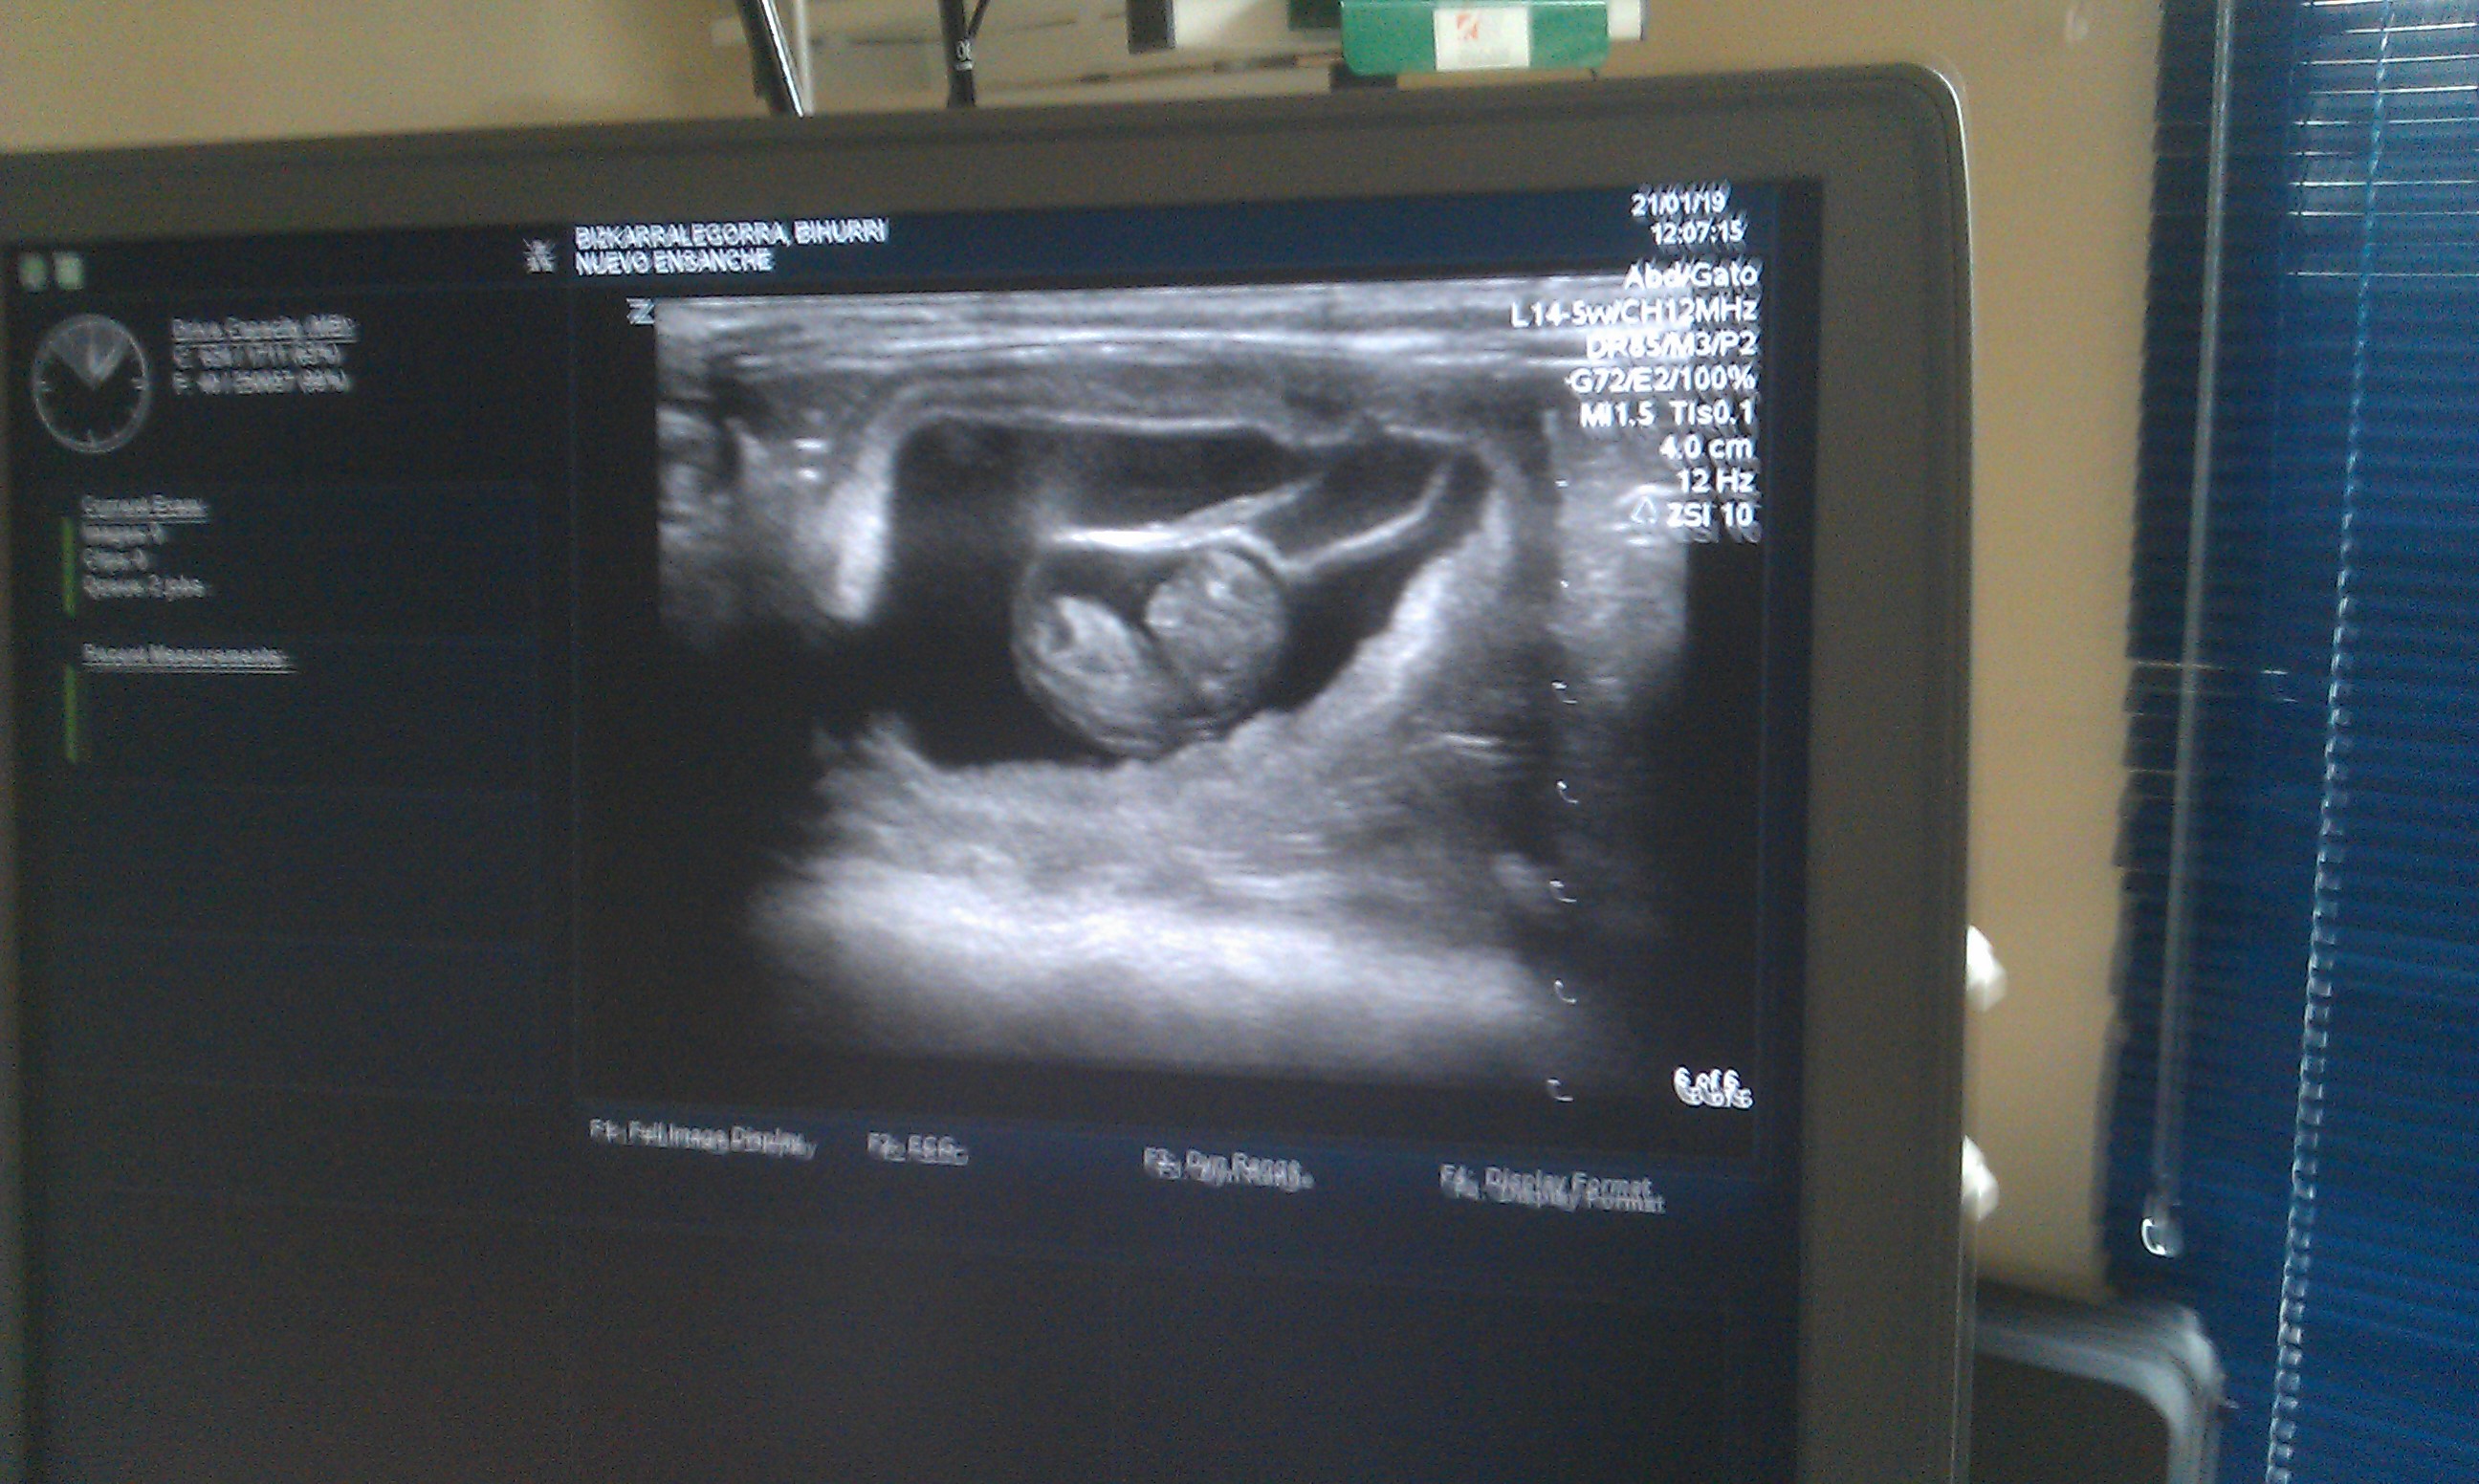

Día de gestación 23

L. 21-1-2019

Las ecografías confirman que 4 crías están en camino.

Bihurri (2d), crías 9c y 9d